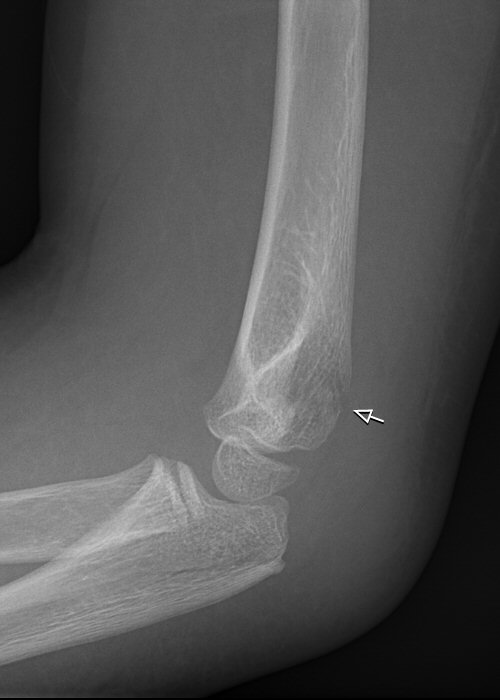

Normal sidobild (vuxet skelett)

Fettkuddar anteriort och posteriort om distala humerus, antyder fraktur (vuxet skelett)